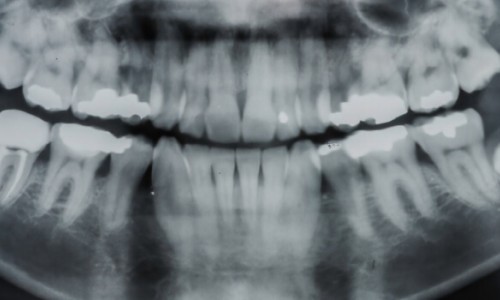

Samsun'da diş tedavileri, sağlıklı bir ağız yapısı ve estetik gülüş için önemli bir hizmet sunmaktadır.

Kanal Tedavisi (Endodonti) Nedir? Ağrılı mıdır?Kanal tedavisi, diş hekimliğinde "endodonti" adıyla bilinen, dişin iç kısmındaki pulpa dokusunun enfekte olduğu veya iltihaplandığı durumlarda başvurulan önemli bir tedavi yöntemidir. Kanal tedavisi, dişin sağlığını korumak, ağrıyı gidermek ve dişi kurt..

Çene Kistleri Neden Oluşur? Tedavi Yöntemleri Nelerdir?Çene kistleri, çene kemiğinde veya diş etinde oluşan, içi sıvı veya yarı sıvı maddeyle dolu anormal boşluklardır. Çene kistleri genellikle diş kökleri çevresinde veya çene kemiğinde ortaya çıkar. Başlangıçta belirti vermeyebilirler, ancak zama..

Samsun-Atakum Gömük Dişler Nasıl Çekilir? Ağrılı mı?Gömük diş, çene kemiğinde veya diş etinde tamamen ya da kısmen gömülü kalan, çıkamayan diştir. Genellikle üçüncü azı dişleri (20 yaş dişleri) gömük kalma eğilimindedir. Gömük dişler ağız içinde baskı, ağrı, enfeksiyon ve komşu dişlere zarar verme..